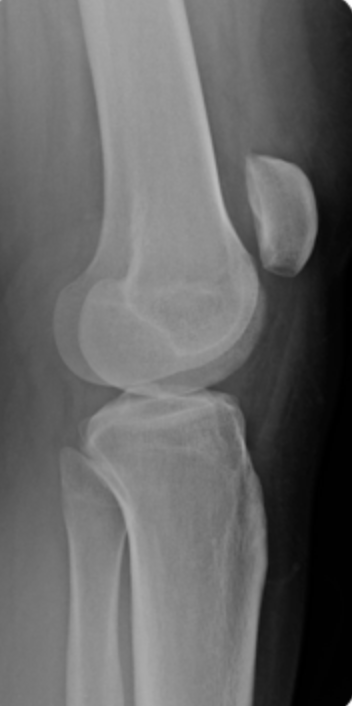

what is this showing

A

patela alta -> patella tendon rupture